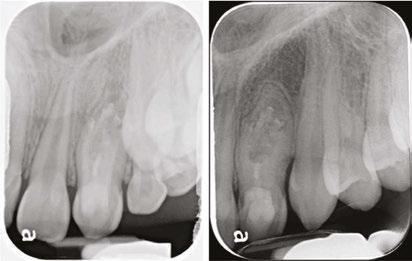

A periapical radiograph demonstrated a DI with an apical radiolucency extending from the mesial aspect of the lateral incisor towards the apex and distal aspect of the central incisor. A slight inclination of the root of the maxillary left lateral incisor was observed in the periapical radiograph.

Considering the irregular anatomy of the tooth, the patient was referred for a CBCT scan.

The CBCT scan confirmed the presence of a Type IIIa invagination and a large radiolucent lesion that was associated with the invagination in the lateral incisor and extended mesially towards the apex of the central incisor. Since the apex of the main canal in the lateral incisor was not involved, it was decided to limit the treatment to the invagination. The diagnosis of the periapex of the previously treated central incisor was unclear; there was either periapical healing or asymptomatic apical periodontitis; therefore, no intervention was done, and the tooth was kept for follow-up.

During the first appointment, a palatal access cavity was prepared under a surgical operating microscope based on the external morphology of the tooth and the CBCT scan. After gaining access to the invagination, the enamel-lined canal was conservatively enlarged using an ultrasonic tip. Biomechanical preparation was based on copious irrigation with 2.5% Sodium hypochlorite (NaOCl) and 17% ethylene diamine tetra-acetic acid (EDTA) and the use of the XP Finisher (FKG Dentaire Sarl, La Chaux-de-Fonds, Switzerland). A calcium hydroxide dressing was placed using a spiral Lentulo, and the access cavity was temporized with Coltosol® (Coltene Whaledent) provisional filling material.

At the second appointment (2 weeks later), the patient was asymptomatic. The invagination was irrigated with 2.5% NaOCl and 17% EDTA, and the enamel-lined invagination was obturated with BC Putty (EndoSequence®, BC RRM™ Fast Set, Brasseler). The access cavity was then filled with a Coltosol F® (Coltene Whaledent) and Fuji Equia glass ionomer (GC America) as a temporary filling to seal the access. One week later, it was replaced by a permanent composite restoration.

One year later, the tooth was asymptomatic, with no tenderness to palpation or percussion, and normal mobility was observed. Radiographic examination demonstrated healing of the lesion. Complete healing was observed around the apex of the central incisor, which was symptom-free, and therefore no intervention was necessary for this tooth.

Figure 1: CBCT scan of the tooth demonstrating the radiolucent lesion surrounding the DI and extending to the apex of the central incisor Figures 2A-2D: 2A. Periapical radiograph of the dens. 2B. Hedstrom file in the invagination. 2C. The obturated enamel lining of the invagination with BC putty. 2D. Healing of the periapical lesion in the 1-year follow-up